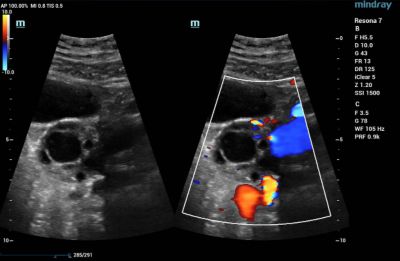

Heart

Echocardiography utilizes a type of CDI that examines the heart and the velocity of blood flow through the cardiac valves and detects any irregularities between the left and right sides of the heart. CDI of the heart can also determine if there is any blood leakage through the valves.

Color Doppler Imaging of Mitral Valve Dehiscence

Color Doppler Imaging of Patent Ductus Arterosus